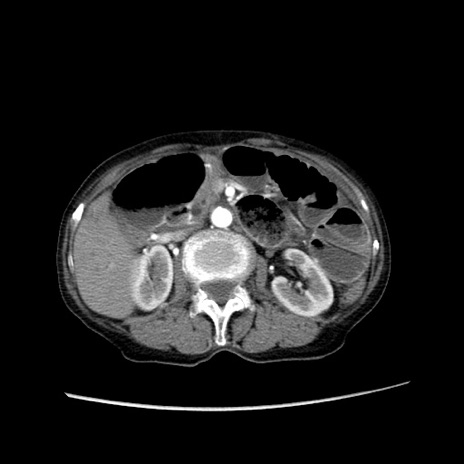

症例25(横断像)

【症例】80歳代女性

【主訴】胸のつかえ感

【現病歴】約9時間前に食後から胸のつかえた感じあり、嘔吐あり、来院。

【既往歴】胃癌(全摘)、胆摘、虫垂炎

【身体所見】心窩部に圧痛あり、反跳痛なし。

【データ】WBC 5700、CRP 0.05